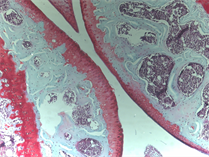

A new method for measuring bone marrow lesions for pain research in people with osteoarthritis

Within the bones of people with osteoarthritis there are often regions called Bone Marrow Lesions (BMLs) which are seen using MRI scanners. They appear to be linked to inflammation and pain. When BMLs are close to the knee joint, they appear to be closely related to osteoarthritis knee pain. Joint tissues are very useful for research aiming to characterise cells and molecules that might be targeted by new drugs in order to relieve pain.

For more details, visit the summary page